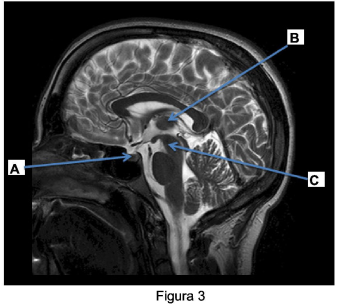

A ressonância magnética do encéfalo fornece dados precisos e anatômicos. A identificação das estruturas anatômicas é fundamental para que o exame seja realizado de forma correta e com qualidade.

A partir da imagem de ressonância magnética mostrada na figura 3 e assinale a alternativa correta: